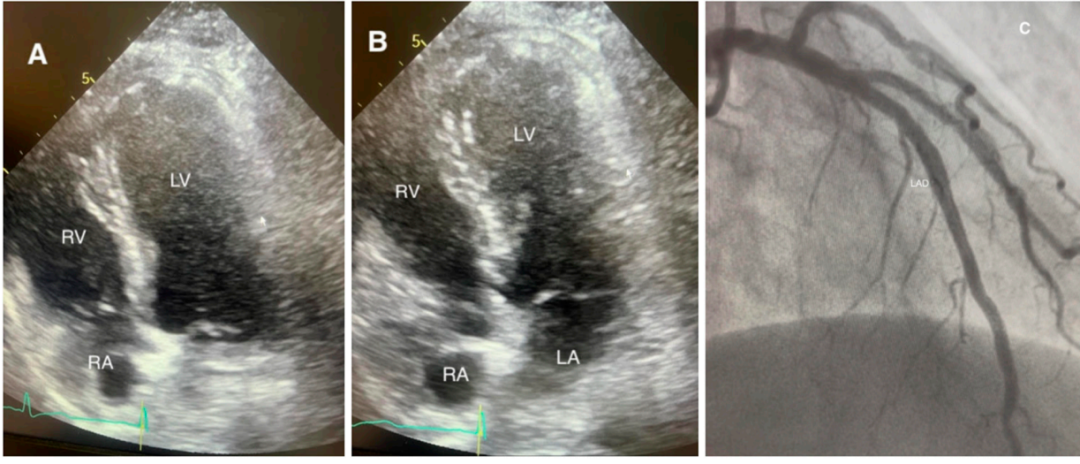

超声心动图:经胸超声心动图可快速识别室壁运动异常的分布模式,评估左心室射血分数和右心室受累情况,是床旁诊断的核心工具;斑点追踪超声心动图可检测到常规超声难以发现的亚临床应变异常,有助于评估病情严重程度和预后;